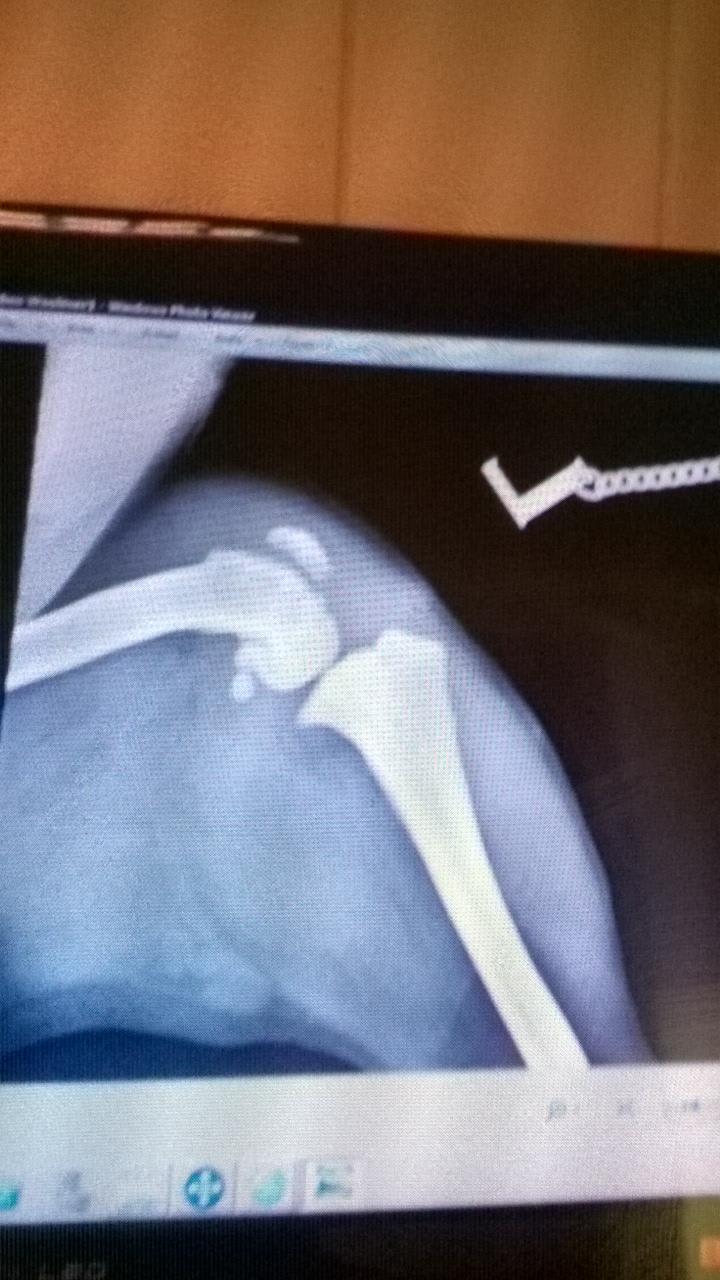

My dog has had a recent x ray and my vet has said that he has Canine Osteosarcoma they wanted to put him to sleep there and then even though no biopsy had been done I refused and bought him back home as he is in good spirits eating well going to toilet regularly just walking carrying the back leg could it be Osteomyelitis as he was also being treated for a fungal infection on his front paw

Osteomyelitis and osteosarcoma can look similar, but there are some distinct characteristics that can be seen on x-rays. The image you provided is very blurry, but I do see the lesion and it does look more suspicious of an osteosarcoma. This is not only because of the location (the knee is a common location for osteosarcoma), but also the fact that it is solitary and has not crossed the joint. However, a biopsy and histopathology is the only way to definitively diagnose the condition. Osteosarcoma is unfortunately a rather severe form of cancer that tends to spread quickly and cause a great deal of pain. If Ben is in good spirits though, then I would not advise euthanasia until he doesn't seem happy anymore. Considering that you are interested in more diagnostics and potentially treatment (there are treatment options for osteosarcoma), I recommend you ask your vet about this, or seek a second opinion. I hope that helps and I'm really sorry to hear about poor Ben.